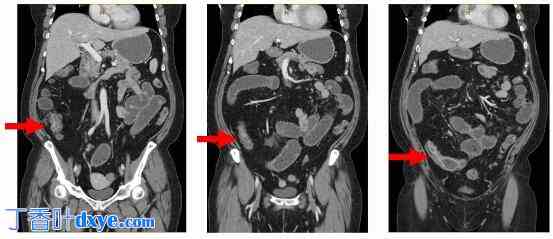

- 55 岁女性

- 10 年克罗恩氏回肠炎病史

- 多种生物制剂治疗失败,复发性阻塞局限于狭窄的回肠

. CT 显示 15 厘米狭窄段,无任何近端病变

CT